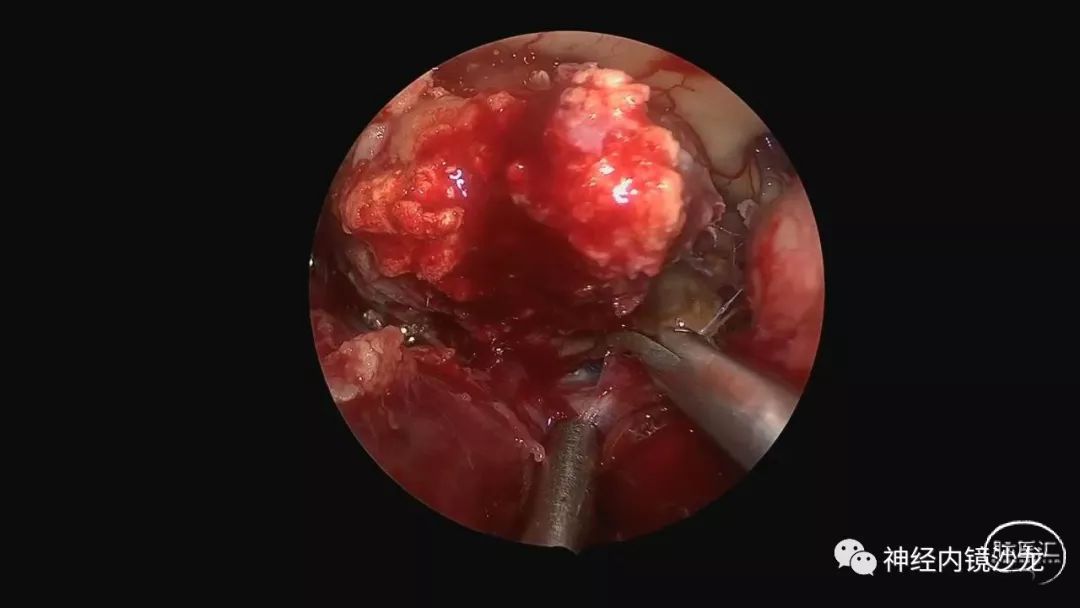

精彩图表

从事神经外科十余年,擅长神经外科肿瘤诊治,尤其是神经内镜微创手术治疗垂体瘤、颅咽管瘤、脑膜瘤等颅底肿瘤